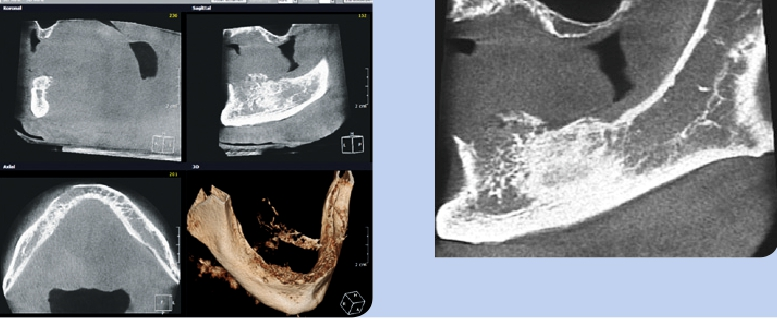

Bei der 79-jährigen Patientin, Nichtraucherin und nicht alkoholabhängig, erfolgte die initiale Diagnosestellung im März 2015. Bei der klinischen Untersuchung zeigte sich eine exophytische Läsion im III. Quadranten und es lag ein starker Verdacht auf ein Plattenepithelkarzinom mit Infiltration des UK vor (Abb. 2 u. 3). Der radiologische Befund ließ eine Tumorinfiltration des perios-talen Gewebes und Arrosion des kortikalen Knochens vermuten, ohne Infiltration der Spongiosa, pT3, pN1, G2 (Abb. 4–8). Die Diagnose lautete: mäßig differenziertes, keratinisiertes, invasives Plattenepithelkarzinom.